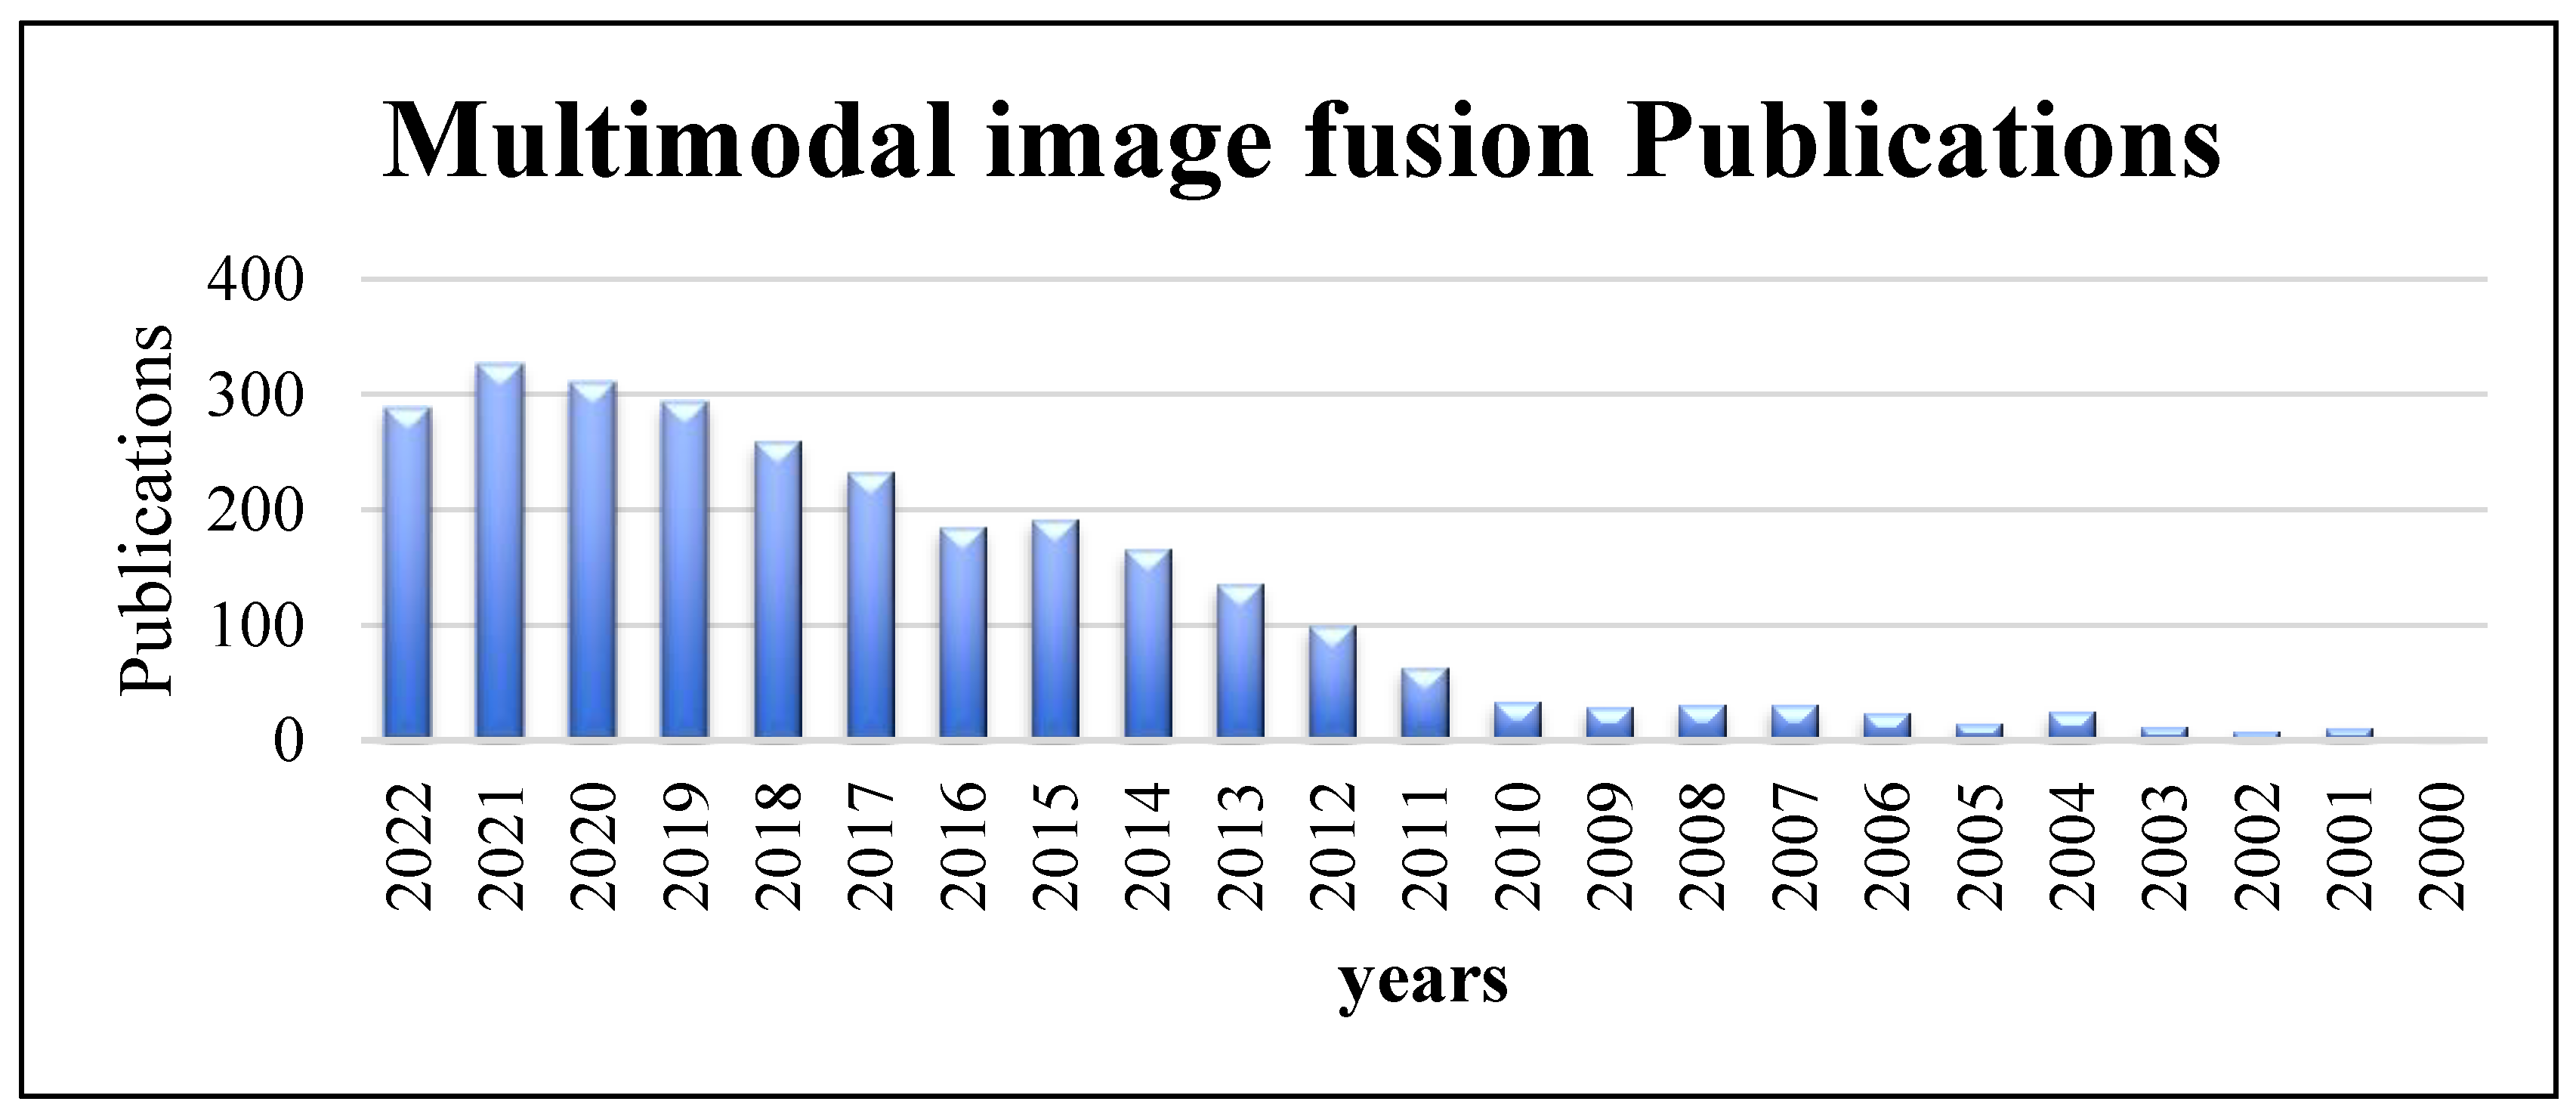

:1. Introduction

3. Fusion Steps